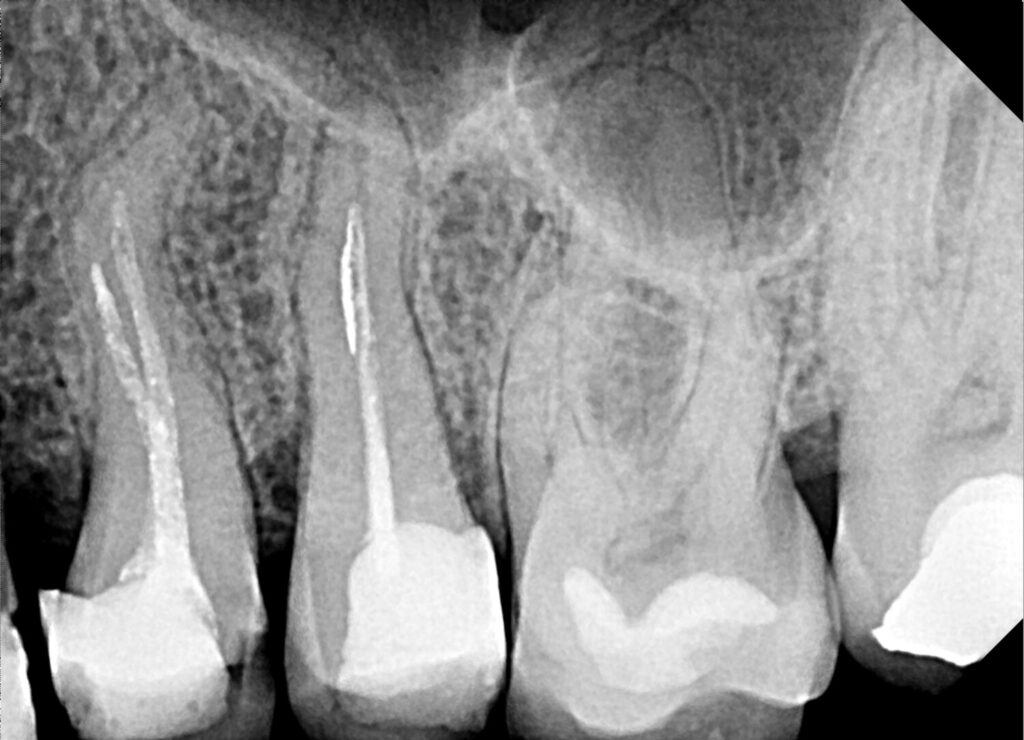

Uveličani radiogram predstavlja napredni oblik rendgenskog snimanja zuba i vilica, koji pruža detaljan i jasan prikaz struktura uvećanih više puta. Za razliku od standardnih rendgenskih snimaka, uveličani radiogram omogućava stomatologu da uoči i najsitnije promene u tkivu, korenu zuba ili vilici, što doprinosi preciznijoj dijagnozi i boljem planiranju terapije.

Uveličani radiogram se snima pomoću specijalizovane digitalne rendgenske opreme koja koristi nisku dozu zračenja i pruža visoku rezoluciju snimka. Snimak se odmah prikazuje na ekranu računara i može se uvećavati po potrebi, bez gubitka kvaliteta slike. Time se omogućava detaljna analiza svakog segmenta zubnog i viličnog sistema.

• – Endodoncija – precizno lociranje problema u korenu zuba

• – Parodontologija – otkrivanje promena u desnima i kostima